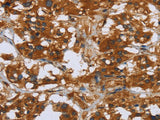

Applications IHC

IHC 1:100-1:300